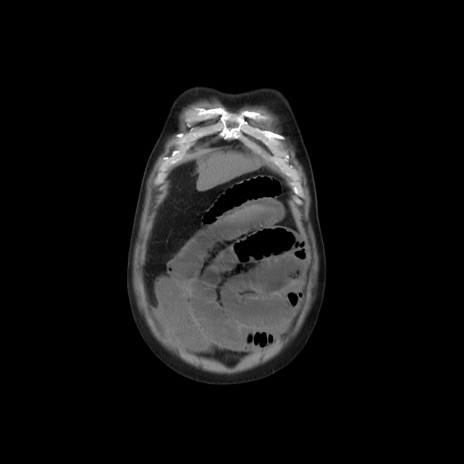

横断像

【症例】 60歳代男性

【主訴】 腹部膨満、嘔吐

【現病歴】5日前頃より倦怠感を認め食事量減少し4日前の朝嘔吐、食事摂取困難となった。 3日前近医受診し点滴施行され整腸剤などを処方された。 当日他院を受診し、腹部膨満著明、炎症反応の上昇(CRP10.8、WBC11200)あり、紹介受診となる。

【身体所見】 意識JCS1 受け答えがはっきりしないBP 111/57mHg、 P 67bpm、、BT35.2°C、SpO2 97%(RA)、 腹部:膨隆、打診で鼓音あり、全体的に圧痛有り、腸蠕動音(-)、反跳痛ははっきりせず。

【データ】WBC 11400、CRP 14.20